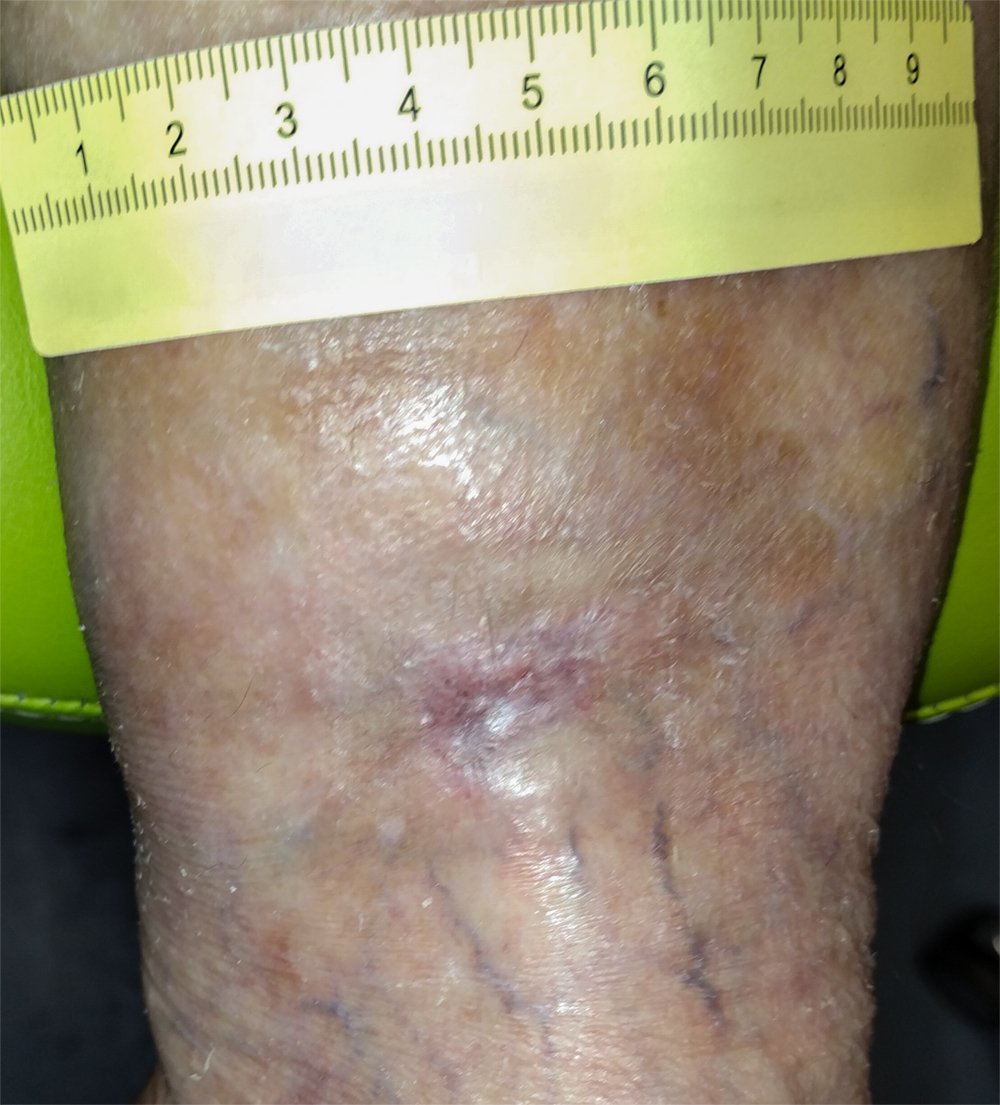

Die Wunde ist 2,9 cm lang, 2,6 cm breit und 2 mm tief. Sie ist mit Fibrin belegt, weist etwas Granulationsgewebe sowie Biofilm auf (Foto 1). Die Exsudation ist mäßig, schleimig, gelblich und geruchlos. Der Wundrand ist stellenweise mazeriert und zeigt Einblutungen. In der Wundumgebung sind leichte Hämatome sichtbar, die Haut ist trocken und teilweise schuppig. Frau F. verspürt nur bei der Wundreinigung leichte Schmerzen. An der linken Wade zeigt sich ein deutliches Inaktivitätsödem.

Foto 1